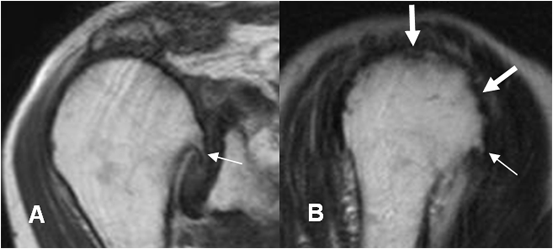

Fig 161 C. Artropatía degenerativa.

A: RM coronal en T1 y B: RM sagital en T2. Cambios degenerativos con formación de osteofitos (Flechas delgadas) y lesiones osteocondrales. (Flechas gruesas).